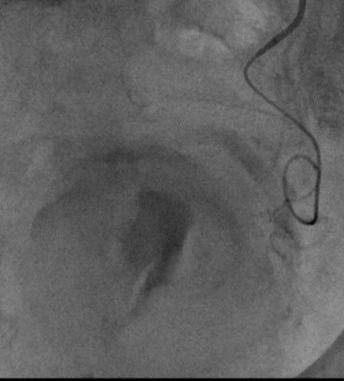

STRIKE-PE interim analysis shows benefit for acute PE patients with syncope

A STRIKE-PE interim analysis of clinical outcomes of acute pulmonary embolism (PE) patients with or without syncope— an indicator of compromised cardiac output and so increased short-term mortality—has found that patients with syncope who had a higher right/left ventricle (RV/LV) ratio at baseline were restored to a condition similar to patients without syncope following treatment with the Lightning Flash (Penumbra) computer-assisted vacuum thrombectomy (CAVT) device.

“SYNCOPE IS A FREQUENT conundrum,” said John Moriarty (University of California Los Angeles, Los Angeles, USA) during his latebreaking presentation of the featured abstract at the Society of Interventional Radiology (SIR) annual scientific meeting (29 March–2 April, Nashville, USA). “Often we are uncertain whether this is a group of patients with acute intermediate risk, or whether they are within a worse group when considering outcomes or at higher risk of [repeated] intervention, so we felt it was important to study this patient cohort,” he stated.

Initially powered to evaluate 600 patients, the STRIKE-PE cohort was extended, subsequently enrolling 1,500 patients. The prospective, international, multicentre study included patients with acute PE symptoms of ≤14 days and an RV/LV ratio of ≥0.9. Patients from this interim analysis with (n=72) versus without (n=228) syncope were compared. Moriarty highlighted that there was a statistically significant difference in Miller score of those ≥12 (91.7% vs. 80.7%, p=0.03) in the syncope cohort, taking this to demonstrate a large clot burden, which

was seen more frequently in patients with syncope than in those without. These patients also presented with a shorter time from symptom onset to venous puncture (47.5 hours vs. 81 hours p=0.04), and a higher RV/LV ratio (1.48 vs. 1.37, p=0.03).

At 48-hour post-procedure followup, RV/LV ratio improved in both groups, however improvement was significantly greater for patients with syncope (0.51 vs. 0.37, p=0.004; 31.7% vs. 25.2%, p=0.002). No significant difference was found between the groups for rate of composite major adverse events within this timeframe, nor concerning 30-day mortality.

“In other words, by imaging

When we look at safety, there are essentially no differences between the patients who had syncope and those who didn’t”

characteristics, [patients with syncope] got better, although both cohorts did well,” Moriarty told SIR 2025 delegates. “When we look at safety,

there are essentially no differences between the patients who had syncope and those who didn’t. We believe this is going to be clinically important because there has been a theory that patients who present with syncope are at increased risk, whether it’s primary safety or device-related safety outcome during the procedure.”

Both groups had reduced dyspnoea via the Borg scale at rest from baseline to discharge, and no significant differences in dyspnoea were reported between the groups following a sixminute walk test at discharge.

“Syncope is a common problem,” Moriarty described. “We believe that it’s an indicator of compromised cardiac output, and then therefore it portends to people who have a bad outcome due to the severity of their haemodynamic instability or right ventricular outflow tract obstruction, with an increase in RV dysfunction at presentation, an increase in short-term mortality and risk of early PE-related adverse outcomes, making this is a very fertile area of evaluation,” he added.

“So far, we believe that the clinical benefits of CAVT that are shown in this study may be especially valuable for patients who present to this theoretically high-risk cohort,” Moriarty commented. Moving forward, he and his team add that there is need to elucidate clinical markers to further the understanding of patients with acute PE.